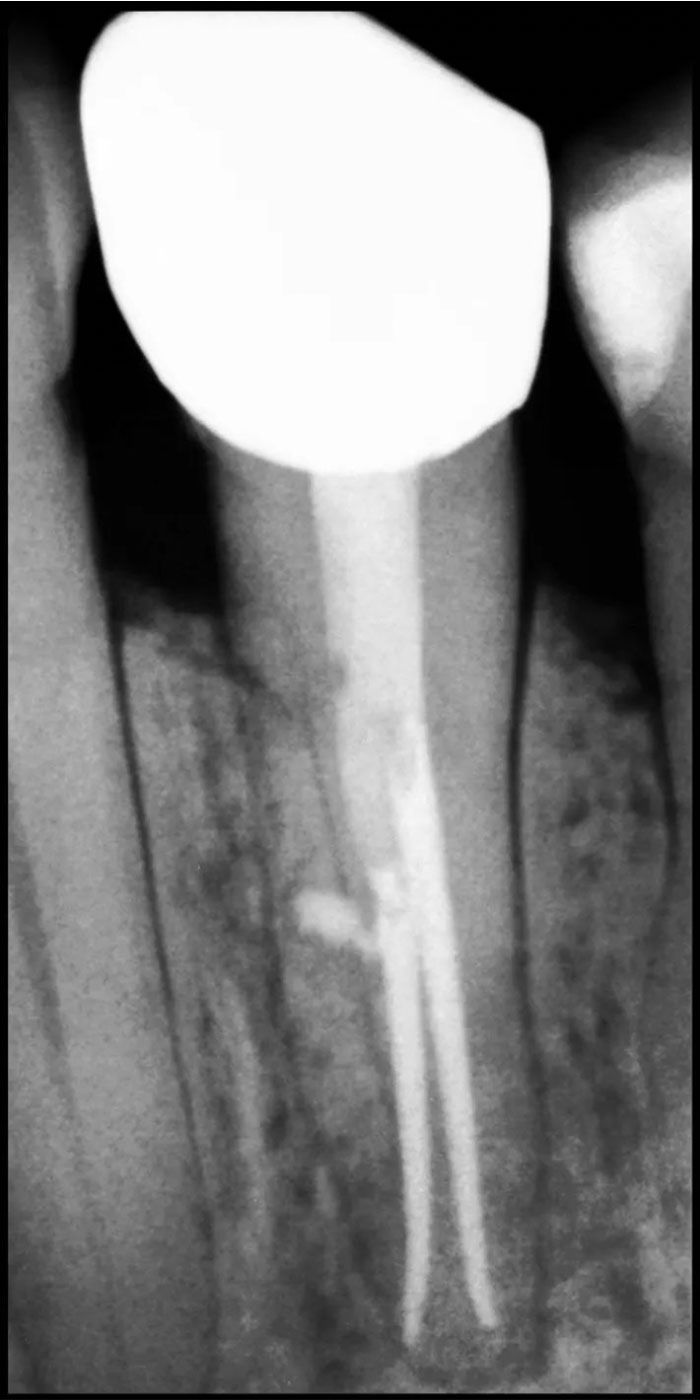

- Our skilled Schenectady root canal dentists will perform a thorough examination and X-rays to assess the extent of damage or infection within the tooth.

- An access point is created in the tooth, and the infected or inflamed pulp is carefully removed to clean and disinfect the root canals.

- The cleaned canals are then filled with a biocompatible material known as gutta-percha, sealing them to prevent further infection.